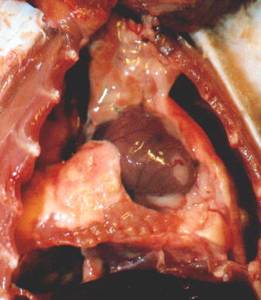

Step 8: To open the chest, continue to cut as

far forward as you can, slightly to the side of center to avoid the

sternum. Cut through the ribs and

spread them open. Observe the lungs. Observe the heart in place, and measure

its length and width. This is

easiest to do with the help of a measuring tool called a drafting divider as it

is hard to get a ruler in the chest (see tools above). You want to measure the heart in place

in the chest because if the heart is abnormally enlarged, it will usually

shrink once it is cut free of the aorta.

This

heart has an enlarged right ventricle. This

heart has a huge enlarged right atrium

Can

you see how it has ballooned out? It which

is caused by high blood pressure

is so

expanded it extends across the top in

the lungs.

of the

heart.